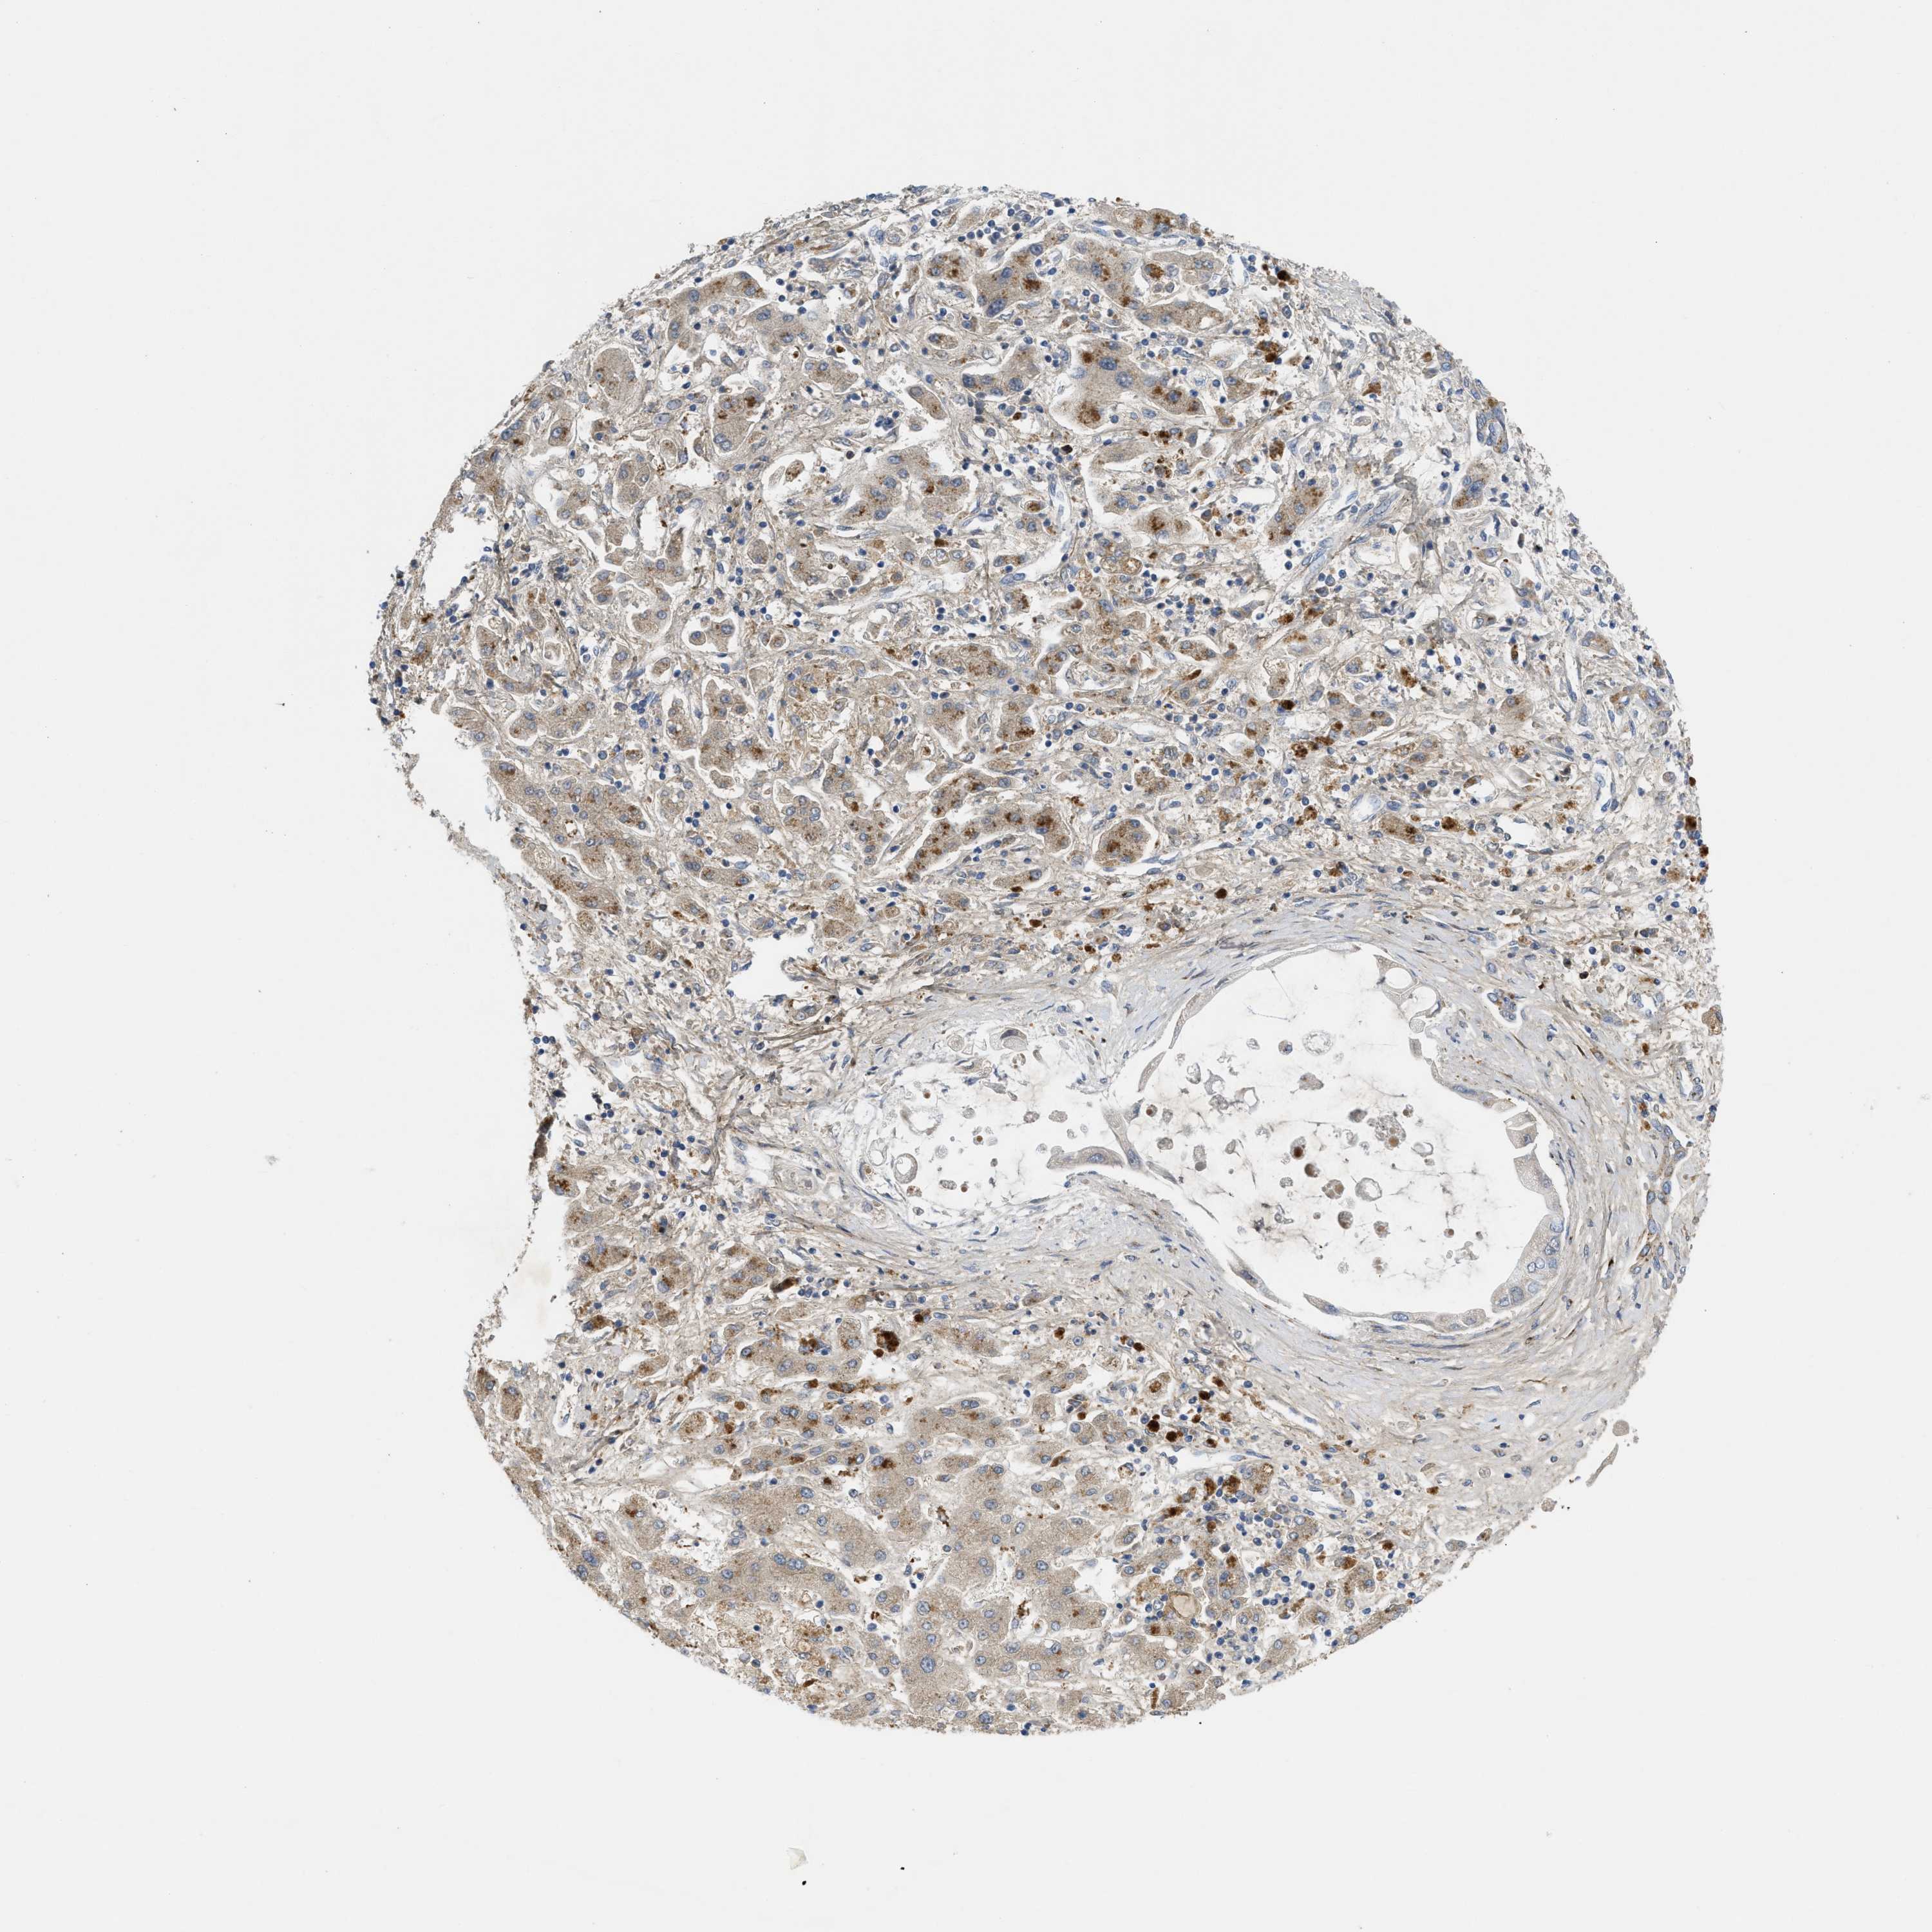

LIVER CANCER - Protein expressioni

A mouse-over function shows sample information and annotation data. Click on an image to view it in a full screen mode. Samples can be filtered based on level of antibody staining by selecting one or several of the following categories: high, medium, low and not detected. The assay and annotation is described here.

Note that samples used for immunohistochemistry by the Human Protein Atlas do not correspond to samples in the TCGA dataset.

Antibody stainingi

Antibody staining in the annotated cell types in the current human tissue is reported as not detected, low, medium, or high, based on conventional immunohistochemistry profiling in selected tissues. This score is based on the combination of the staining intensity and fraction of stained cells.

Each image is clickable and will lead to virtual microscopy that enables deeper exploration of all samples and also displays staining intensity scores, fraction scores and subcellular localization as well as patient and tissue information for each sample.

Antibody HPA018821

Staining

High

Medium

Low

Not detected

Intensity

Strong

Moderate

Weak

Negative

Quantity

>75%

75%-25%

<25%

None

Location

Nuclear

Cytoplasmic/membranous

Cytoplasmic/membranous,nuclear

Cholangiocarcinoma

Carcinoma, Hepatocellular, NOS